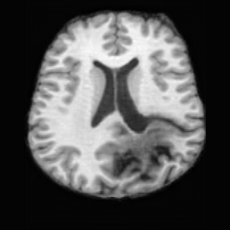

Anomaly Consistency Guidance. Fig. 6 demonstrates the effectiveness of the proposed Anatomy Consistency Guidance (ACG) on bidirectional editing. Without ACG, the generated brains exhibit noticeable and unrealistic anatomical deformations in non-lesion regions (arrow-indicated), leading to structural inconsistencies between the edited and original brains, as shown in the corresponding difference maps. After incorporating ACG, the model effectively constrains editable modifications within pathological regions, while preserving the remaining anatomy. Tab. 4 further reports their quantitative performances: removing ACG leads to a substantial degradation in all L1, PSNR, and SSIM scores, reaffirming the critical role of ACG in achieving more accurate and structurally consistent reconstructions.

Lesion Consistency Guidance. Fig. 7 illustrates the impact of Lesion Consistency Guidance (LCG) for healthy-to-pathology editing. Without LCG, the generated lesion regions appear blurry around lesion boundaries, and the pathological patterns are less distinct, resulting in ambiguous lesion localization and weak pathological expression. Incorporating LCG produces lesions with more precise localization and well-defined shapes that better align with the given lesion masks, as well as textures and contrasts that exhibit stronger pathological characteristics. These results demonstrate that LCG effectively enforces lesion-aware conditioning, enhancing both spatial and semantic consistency of the generated pathological regions.